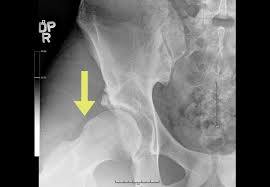

Garden Clasification System for femoral neck fracture

Stages

Grading for Slipped Capital Femoral Epiphysis (SCFE)